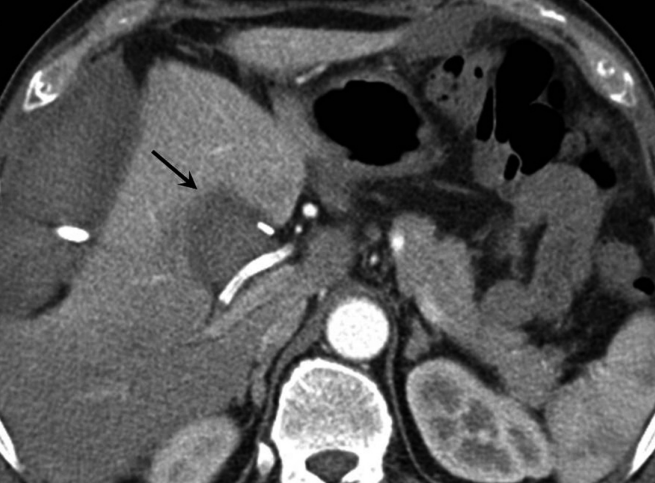

복강동맥조영술에서 우간동맥의 분지부에 인접한 위치에 가성동맥류를 확인하였다(Fig. 2A, B). 6F Shuttle guiding catheter(Cook, Bloomington, IN, USA)로 교체 후에 Stent-graft(4×26mm, JoStent GraftMaster®, JoMed, Germany)를 가성동맥류가 있는 우간동맥에 위치시키고, 풍선카테터(Ultra-thin Diamond,Boston Scientific, Galway, Ireland)를 사용하여 확장시켰다. 시술 직후 시행한 복강동맥조영술에서 동맥류는 관찰되지 않았다(Fig. 2C).

Fig. 2

Celiac (A) and hepatic angiogram (B) show the pseudoaneurysm (arrows in A and B) at distal part of the right hepatic artery near the origin of the right posterior hepatic artery. (C) On hepatic angiogram after stent-graft placement (arrow), the pseudoaneurysm is completely excluded.